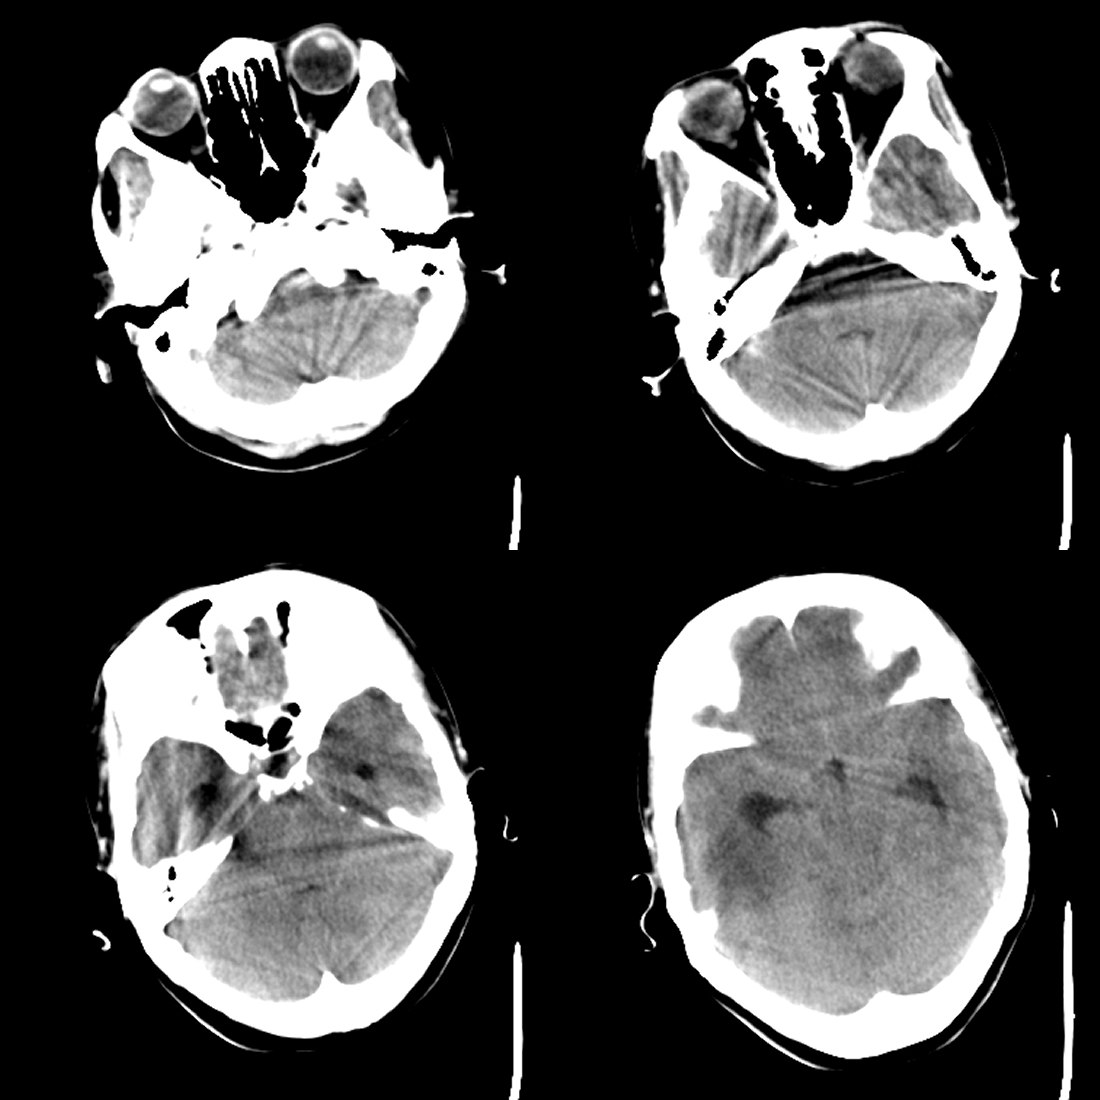

53岁女性,反复头痛,病史较长,今日加重数小时就诊。暂未作增强。

1)考虑蛛网膜下腔出血。2)右侧幕上半球相当于右侧侧脑室三角区区域巨大囊性占位性病变;考虑蛛网膜囊肿,不排除囊性胶质瘤。3)脑积水。4)大脑镰下疝。

考虑蛛网膜囊肿,右侧侧脑室后角及三角区受压变小,中线向左移位。病变与脑室不相通。没有脑积水!!